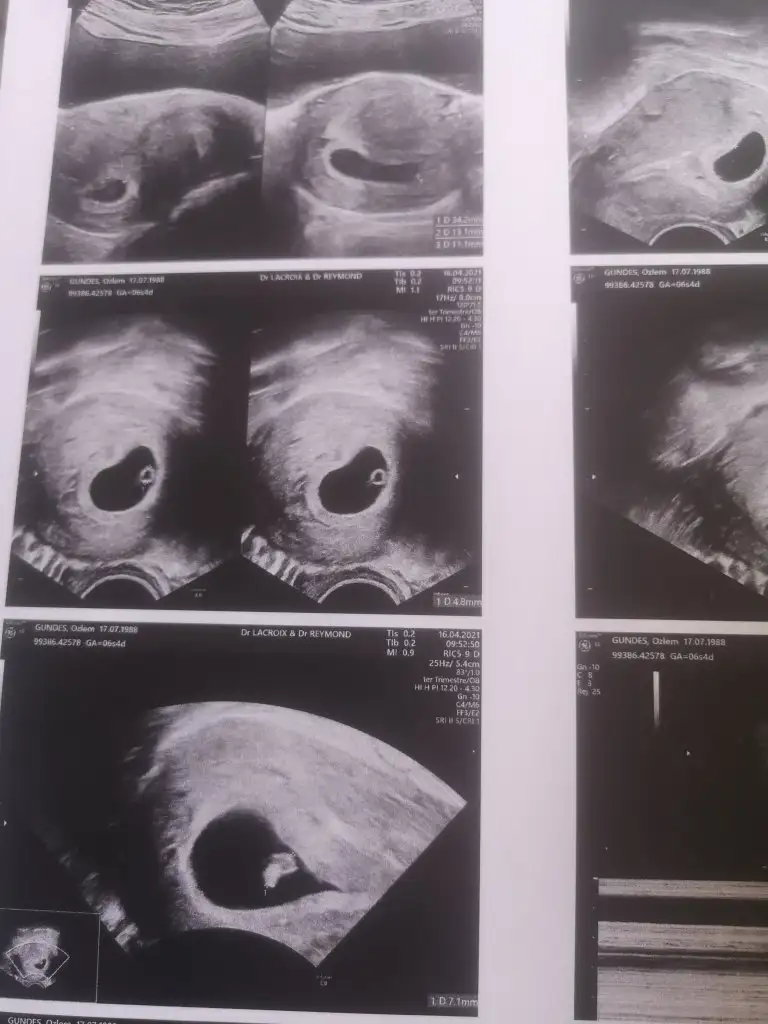

Selamlar herkese hayırlı ramazanlar. Nette dolaşırken denk geldim e aranıza katılmak istedim😊hersey Allahtan benimde bakarmisiniz 6+4 haftalık vajinal ultrason çok merak ediyorum 🙉

Eklentiler

• 16188343886964929173605816109692.webp

16188343886964929173605816109692.webp

33 KB · Görüntüleme: 96

• 16188344093662920169798443939039.webp

16188344093662920169798443939039.webp

37,2 KB · Görüntüleme: 81